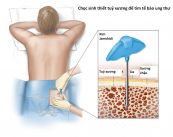

Sinh thiết tủy xương và hút tủy cung cấp khác nhau, nhưng bổ sung, thông tin về tế bào tủy xương. Hai thủ tục này thường cùng nhau, trong một số trường hợp, có thể chỉ cần hút tủy. Hãy cùng eLib tìm hiểu cụ thể hơn nhé